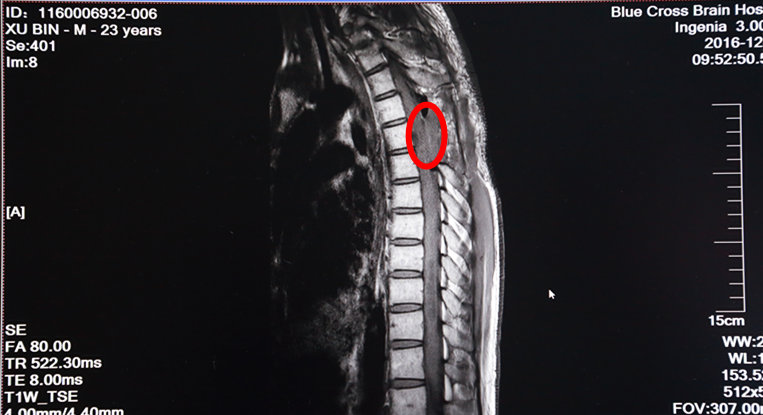

次日,手術進行。術中,在全麻下打開硬脊膜,手術顯微鏡下,脊髓表面見大量迂曲的血管團,選擇血管相對稀少而功能不是很重要的區(qū)域切開薄如薄紙的脊髓,小心沿腫瘤邊緣分離并逐次切斷供應腫瘤的血管,順利地完成了腫瘤的全切除。術后增強MRI示腫瘤已經(jīng)全部切除了。

術后MRI增強掃描:紅圈內(nèi)腫瘤物已消失